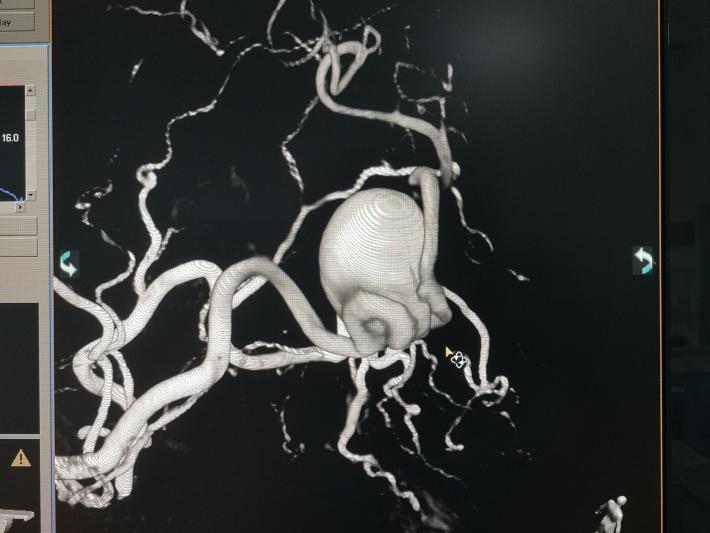

患者女性,70岁,系发现左侧眼睑下垂伴活动障碍一年余入院。外院头颅MR见左侧鞍旁类圆形占位,不能排除动脉瘤,我科行全脑血管造影术,明确为左侧海绵窦段巨大动脉瘤。

术中见海绵窦水平段巨大动脉瘤,瘤体造影剂明显滞留,且影响远端左侧远端血流。但前交通开放,对侧颈内动脉可完全代偿血流。